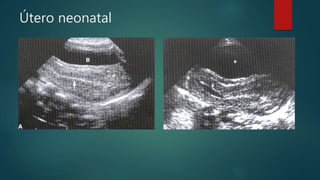

 Útero neonatal

• Mayor que el útero infantil

• Estimulación hormonal maternal

• Endometrio eco génico

Útero neonatal